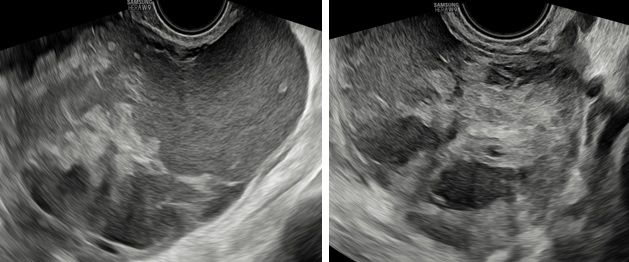

Hình 2: Mặt cắt dọc và ngang qua ngã âm đạo thấy khối u có phản âm hỗn hợp, bên trong có nhiều mảng phản âm dày, di động khi di chuyển đầu dò, giúp hướng đến bản chất xuất huyết.

– Siêu âm: Tử cung và buồng trứng (T) bình thường, buồng trứng (P) không quan sát thấy. Từ cùng đồ sau lan qua hố chậu (P) có 1 khối echo hỗn hợp không đồng nhất, kích thước# 105x 98x 59 mm, bên trong có nhiều mảng echo dày bờ không đều, di động khi di chuyển đầu dò, có tăng sinh mạch máu mức độ 3 Ở ngoại vi khối này có hình ảnh mô buồng trứng bình thường. Dịch cùng đồ# 8 mm.

– Chẩn đoán siêu âm: Theo dõi khối huyết tụ thành nang (HTTN) chưa loại trừ khả năng: u đơn thùy buồng trứng (P) có mảng xuất huyết bên trong.